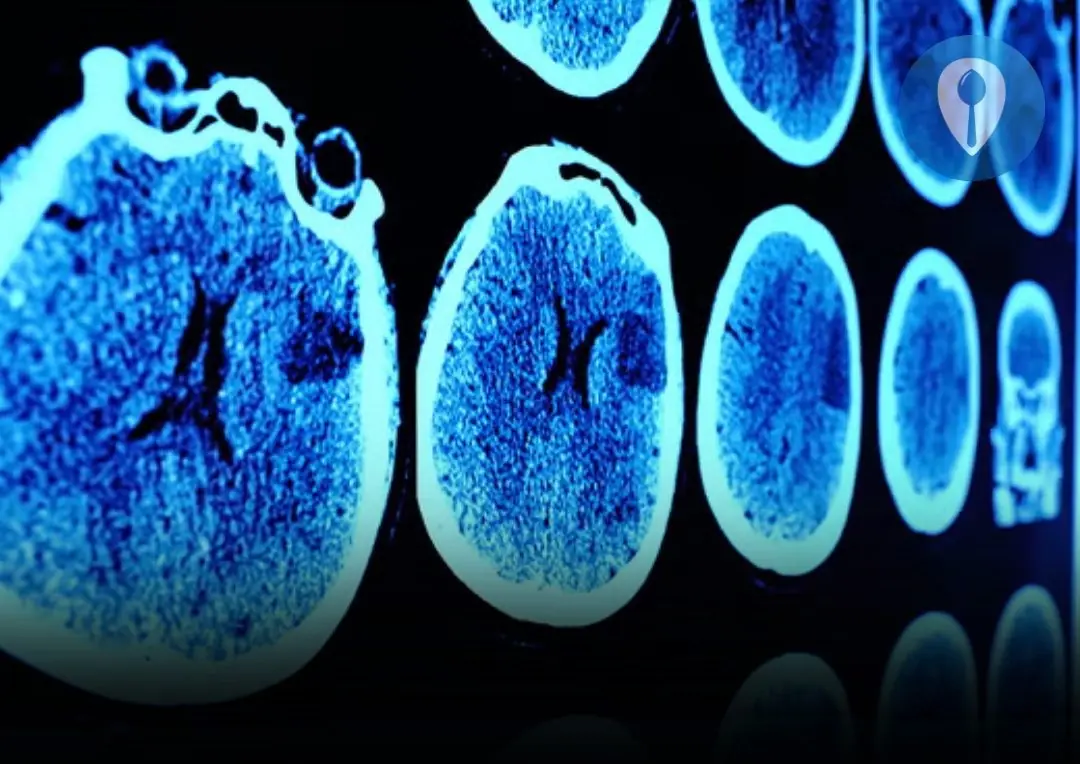

Is Onion the “Uric Acid Killer”? Foods to Avoid to Reduce Stroke Risk

Onions are a common ingredient in kitchens worldwide, but recently they’ve been labeled by some as a “uric acid killer.” Is this claim true, or just another health myth? Understanding how onions affect uric acid—and how diet influences stroke risk—can help you make smarter choices for your health. Here are eight important facts you should know.